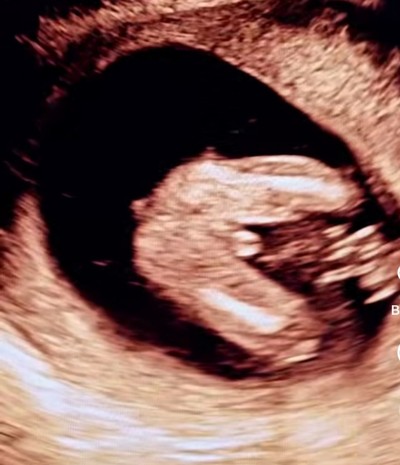

Cinsiyet tahmini yapabilirmisiniz

Gebelik haftası 20

Canım bacak arası meydanda daha nasıl belli etsin yavrucak %100 erkek cinsiyeti öğrenince yaz lütfen

%100 kızzz.bu bellı

Kesinlikle %100 kız net açık göstermiş ortada